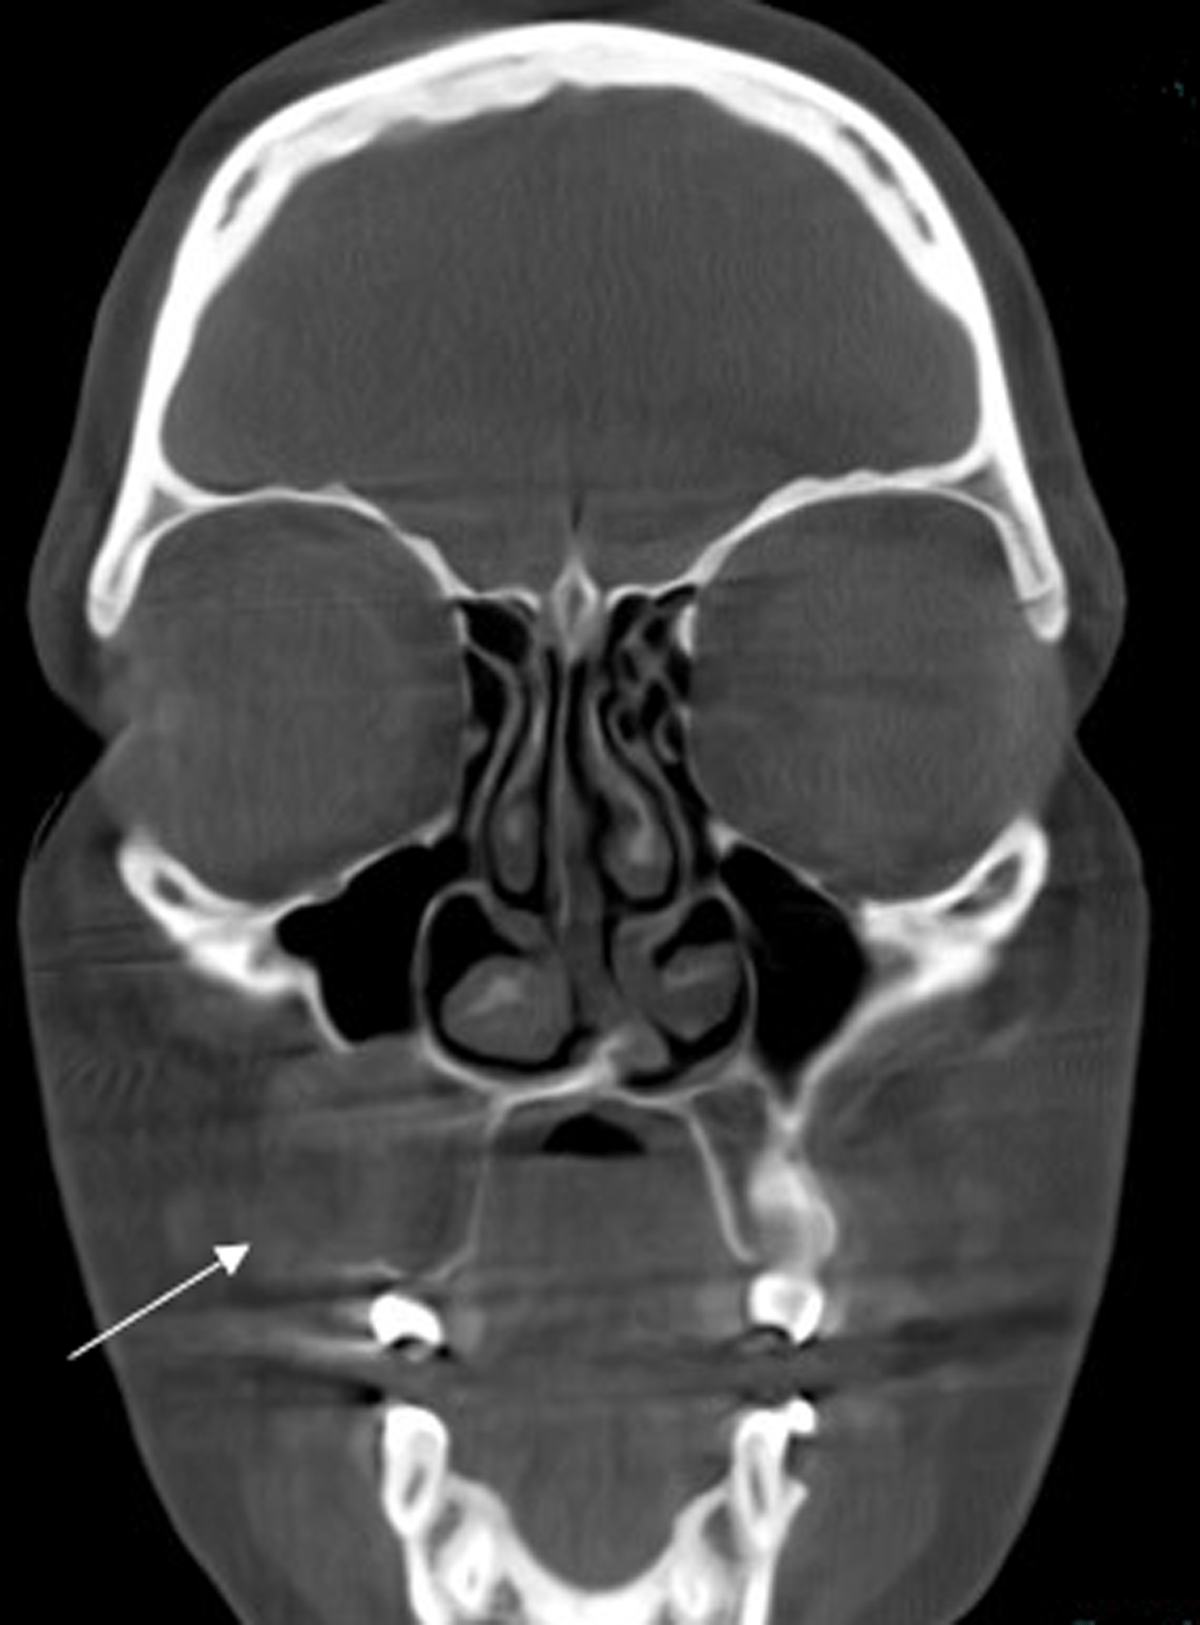

Cone-beam computed tomography (CBCT) scan showed a sharply demarcated hypodense nodule (2.1 cm) centred in the space between the roots of tooth element 14 and 15 (Figures 1 and 2).

Figure 2